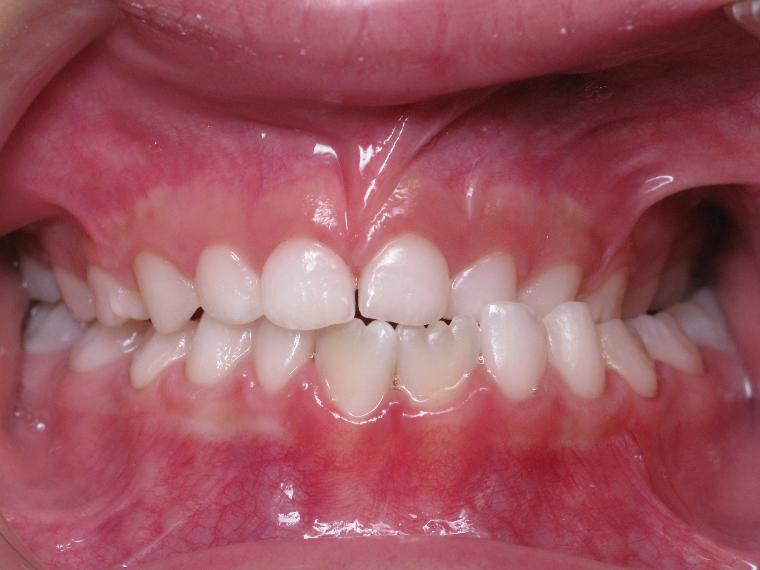

9. inversé gauche 6 ans

inversion des dents posterieur cote gauche

bilan début et fin de traitement